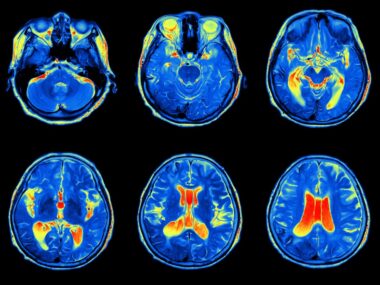

Genzyme presented new magnetic resonance imaging (MRI) data from the Lemtrada® (alemtuzumab) clinical development program on April 23, 2015, at the 67th American Academy of Neurology (AAN) Annual Meeting. The company showed that in the extension phase of two Phase III trials (years 3 and 4), the drug continued to protect the nervous system from damage. Through year four, drug side effects were the same as those observed during the first two years.

Phase III trials of Lemtrada consisted of two-year studies comparing Lemtrada with high-dose subcutaneous interferon beta-1a (Rebif®). The trials were called CARE-MS I and CARE-MS II (CARE stands for Comparison of Alemtuzumab and Rebif Efficacy in Multiple Sclerosis). In Phase III pivotal studies, Genzyme researchers studied people with relapsing remitting multiple sclerosis (RRMS) treated with Lemtrada. The investigators took magnetic resonance imaging (MRI) measurements to assess nervous system damage.

The scientists found that nervous system damage (brain atrophy) decreased over four years among Lemtrada patients in CARE-MS I. In the second trial, CARE-MS II, nervous system damage decreased over three years and was low in the fourth year. In year three and four, brain volume loss was less than during the first two-years for both studies. Treatment with Lemtrada in both studies decreased the risk of developing new lesions compared to interferon beta-1a. About 70% of participants had no new lesions in years 3 and 4 for both studies.